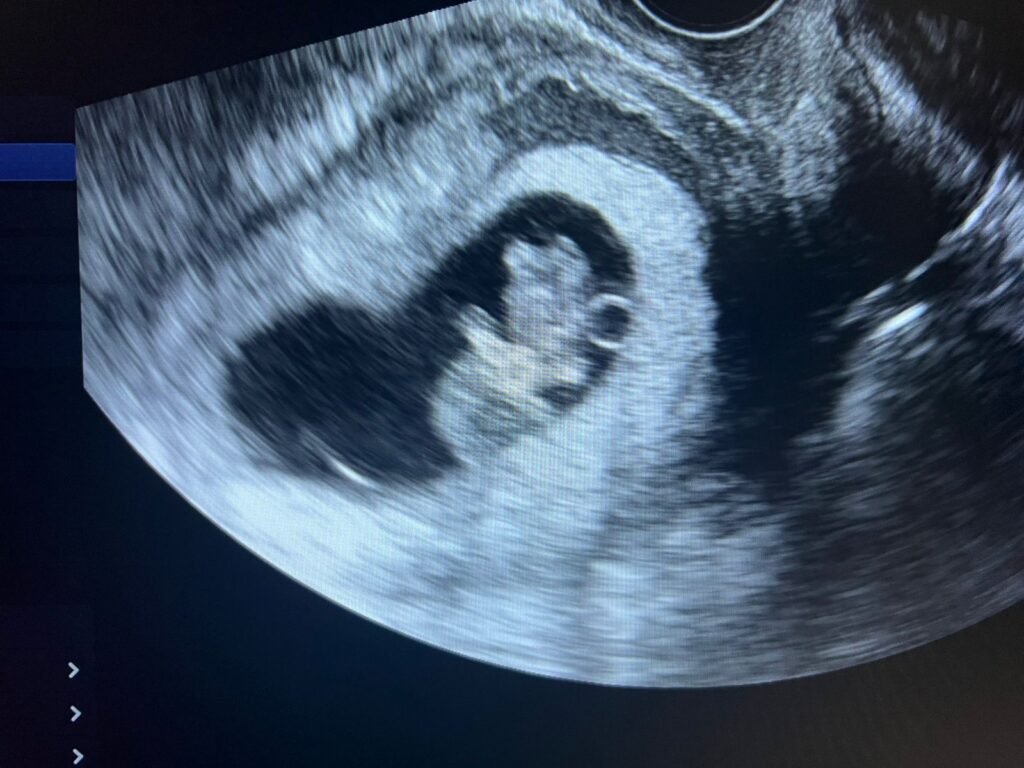

La dirección del centro de salud detalló que, además del nuevo servicio de Doppler periférico arterial y venoso, así como Doppler carotídeo, el hospital pone a disposición de la comunidad una amplia gama de estudios sonográficos que incluyen: abdominal, obstétrica, ginecológica (transvaginal y suprapúbica), de mama, tiroides, próstata (transrectal y transabdominal), testicular, de partes blandas y músculo esquelético.